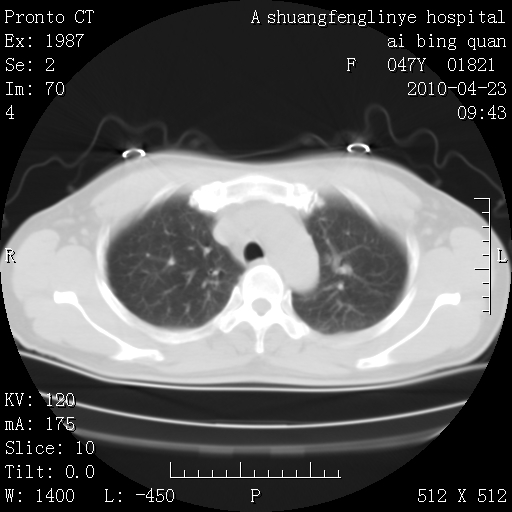

标题: CT25944:胸痛、气短、前几日高烧!肺Ca?请会诊! [打印本页]

标题: CT25944:胸痛、气短、前几日高烧!肺Ca?请会诊!

双肺多发结节,考虑转移瘤,肺癌肺转移不除外

双肺多发结节,部分密度较高,最大结节边缘光滑。临床有“胸痛、气短、前几日高烧”病史。首选考虑:右肺感染性病变!建议积极消炎后复查!